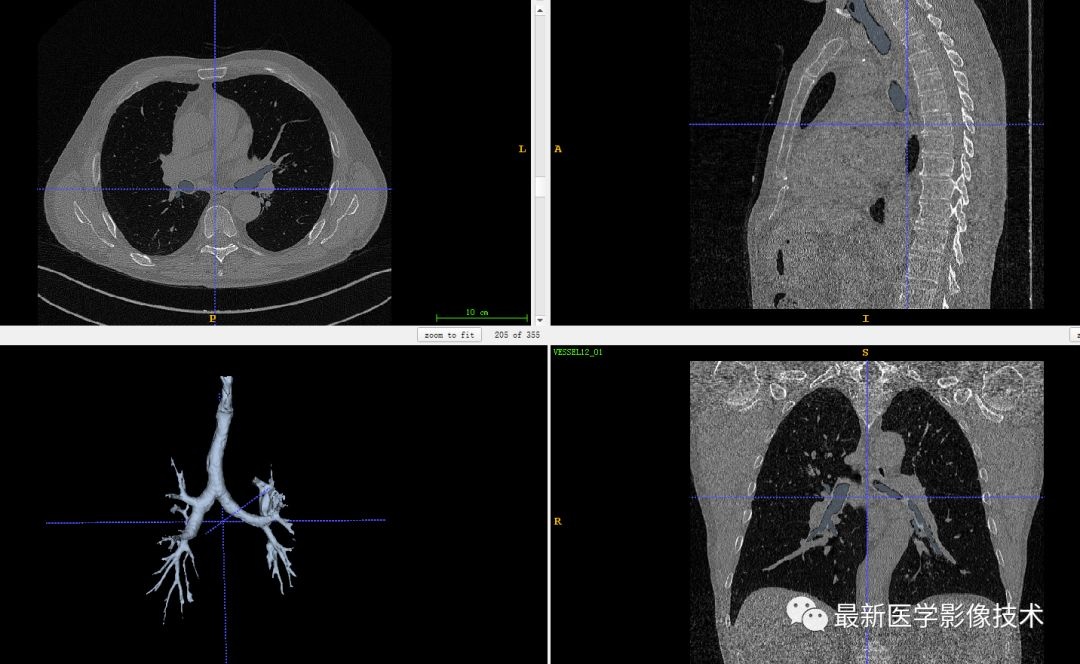

最后,我们将该区域与原始图像进行结合,生成肺部气管三维模型结果。